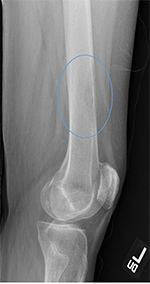

Radiographic examples